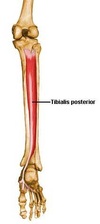

Origin and insertion of Tibialis posterior

O: Posterior surface of interosseous membrane; tibia and fibula

I: Navicular

Innervation and action of tibialis posterior

I: Tibial n

A: plantarflexes and inverts foot